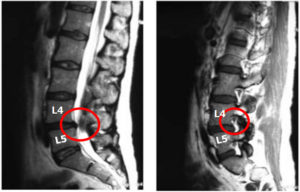

Грыжа межпозвоночного диска L4 L5

Диагноз грыжа диска L4 L5 ставят, когда развивается патологическое нарушение в области этих позвонков.

Такое нарушение встречается в половине случаев поражения поясничного отдела, при этом заболевание характеризуется выраженными симптомами, при которых человек частично утрачивает способность нормально передвигаться.

Межпозвоночная грыжа 4 и 5 позвонков

Межпозвоночная грыжа диска l4 l5 создает проблему именно между этими позвонками поясничного отдела позвоночника. В медицинской практике 50% случаев приходится как раз на эти сегменты.

Более половины случаев возникновения межпозвоночных грыж приходится именно на поясничную область позвоночника. Грыжа диска L4 L5 – наиболее распространенная патология, возникающая в поясничной области позвоночника.

При образовании выпячивания в этой области существует большая опасность чрезмерного пережатия нервных окончаний, что обуславливает уменьшение чувствительности и возникновение атрофии мышц.